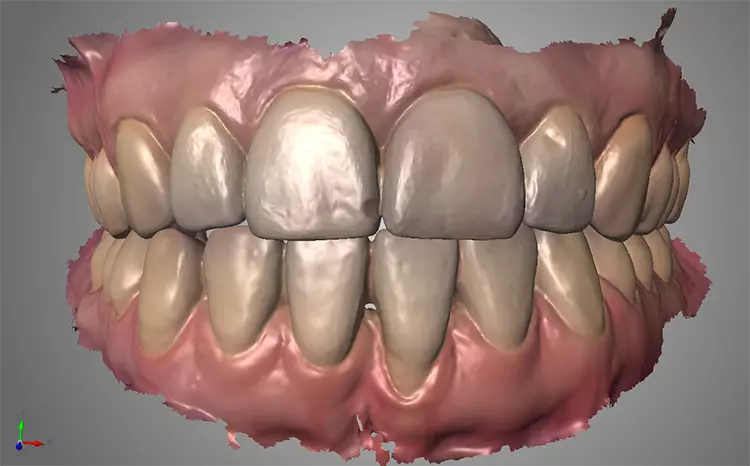

In Vorbereitung auf die Implantatplanung und das CAD/CAM-Herstellen der temporären Krone erfolgte eine digitale Datenerfassung mit dem Intraoralscanner (Trios 3, 3Shape). Der Datensatz der Ausgangssituation sollte später bei der CAD-Konstruktion hilfreiche Informationen liefern (Abb. 3). Mit dem Scan ist die Ausgangssituation digital archiviert und steht jederzeit zum Abruf bereit. Zudem wurde ein DVT für die Planung der Implantatposition am dreidimensionalen Bild vorgenommen und der DICOM-Datensatz in die Implantatplanungssoftware importiert (Abb. 4 und 5).